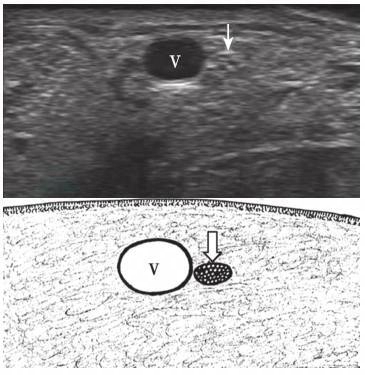

腓肠神经:检查腓肠神经时,探头置于小腿中后部,可首先显示小隐静脉的短轴,在其周围寻找筛网样结构的腓肠神经(图 10-40)。

图10-40 腓肠神经声像图

V:小隐静脉;箭:腓肠神经